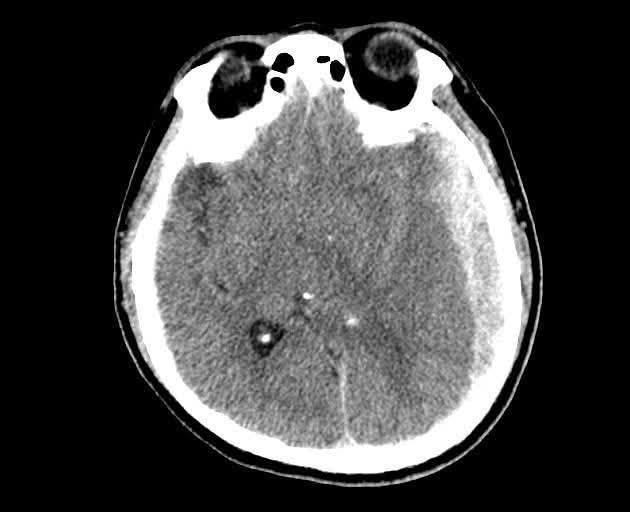

Hình ảnh tổn thương trên phim chụp - Ảnh BVCC

CT sọ não cấp cứu ghi nhận: Tụ máu dưới màng cứng hai bán cầu, bên trái dày tới 18 mm; Xuất huyết dưới nhện rải rác hai bán cầu; Đường giữa lệch 15 mm – dấu hiệu chèn ép não nghiêm trọng; Vỡ xương thái dương phải, xương đá trái, kèm tụ dịch sào bào chũm.

Chẩn đoán xác định: Chấn thương sọ não nặng; Tụ máu dưới màng cứng hai bán cầu; Xuất huyết dưới nhện; Vỡ xương sọ.